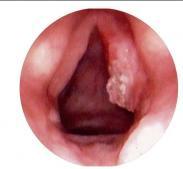

喉白斑病是喉粘膜上皮片狀角化增生,常認為是癌前病變,多發生聲帶,可能和吸煙,用聲不當,慢性喉炎,維生素或微量元素的缺乏有關,主要病理變化為上皮增生,表皮細胞角化...